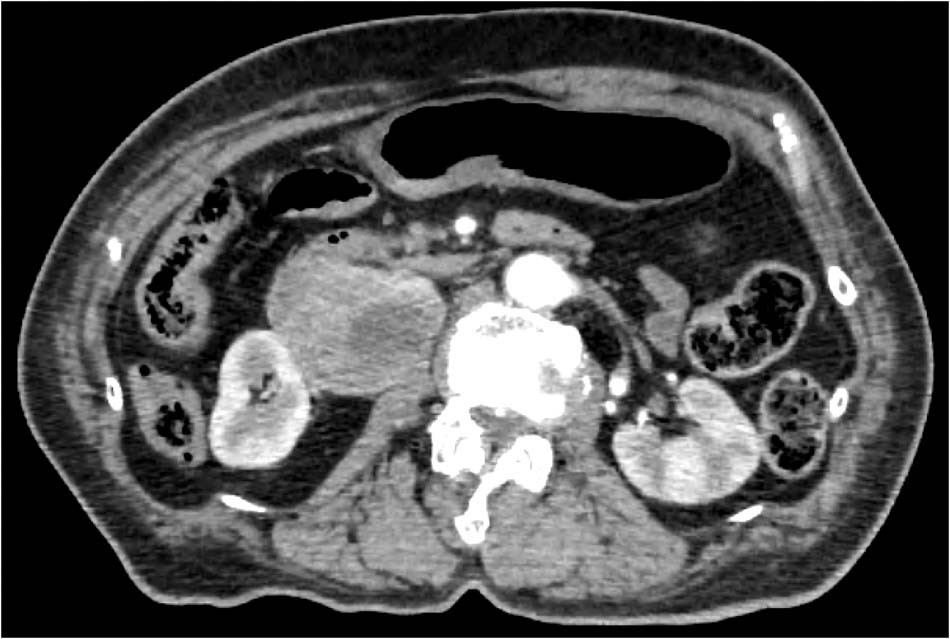

Fig. 1

CT scan showing a defined mass (62 × 50 mm) at the hilum of the right kidney. At the emergency department, as diagnosis of PPGL was not suspected, CT scan was done with contrast enhancement